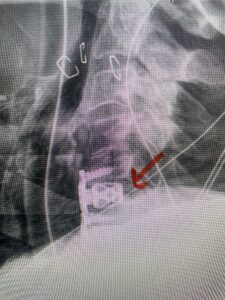

This 61-year-old female with a history of severe osteoporosis and a prior history of a laminectomy from l2-S1 with an L5-S1 instrumented fusion, presents with progressive low back pain and right lower extremity radiculopathy. MRI revealed a grade 1 L2-3 spondylolisthesis with severe stenosis mainly from severe right L2-3 facet joint hypertrophy which was compressing the right L3 descending nerve root. (Fig. 1). She had failed conservative management consisting of physical therapy and pain management with epidurals. She underwent an L1-3 revision laminectomy where we had to dissect a plane underneath the inferior aspect of the L2 lamina. We performed an instrumented fusion at L2-3 with special hydroxyapatite-coated screws to improve fixation to surrounding bone given here severe osteoporosis (Fig. 2) This worked out well and the patient had an uneventful recovery with relief of her leg pain.

Figures 1a: Sagittal and axial T2-weighted lumbar MRIs demonstrating a grade 1 L2-3 spondylolisthesis (red arrow) with severe stenosis secondary to right L2-3 facet hypertrophy (red arrow).

Fig 1b: Note the left L2-3 facet joint (blue arrow) is normal in size compared to the right (red arrow)